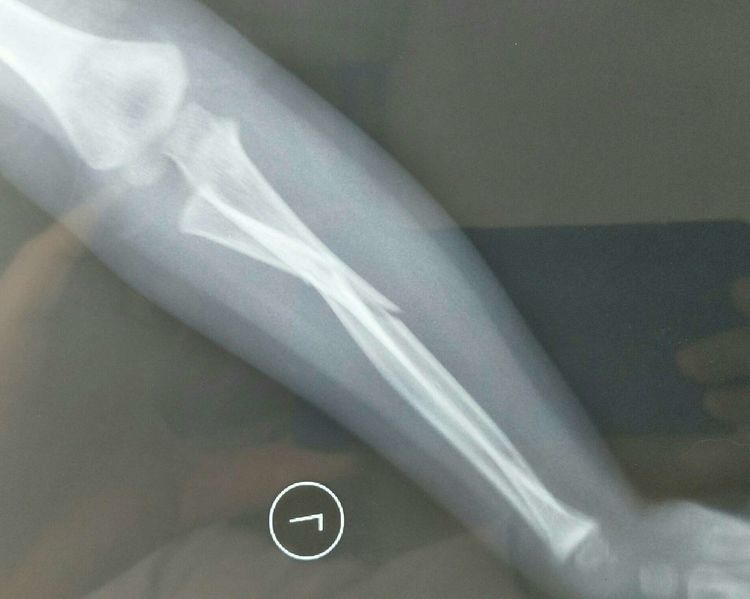

患儿张×,男性,3岁2个月,病案号(2003072528),主因左前臂摔伤后肿痛、畸形、活动受限3小时入院,查体:左前臂肿胀、畸形,左前臂旋转受限,左肘关节屈伸活动受限,左手各指活动尚可。

扎鲁特旗人民医院左前臂正侧位片示:左前臂双骨折,骨折端成角移位明显,入院诊断:左前臂双骨折,因骨折端成角移位明显,而且考虑桡骨小头可能存在半脱位,手法复位失败率高,故拟行手术治疗。